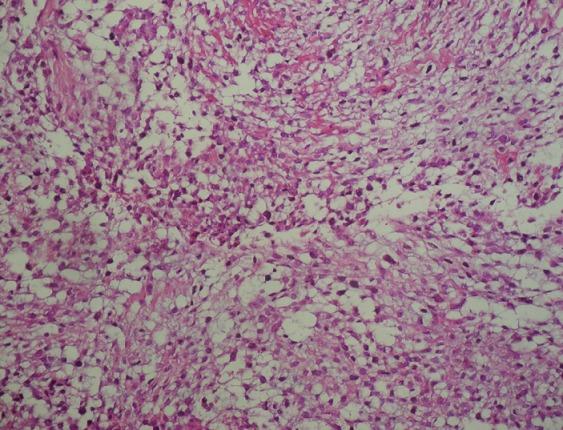

Sinonasal glomangiopericytoma: case report with emphasis on the differential diagnosis.

Arch Pathol Lab Med. 2010 Oct;134(10):1444-9. doi: 10.5858/2010-0233-CR.1.